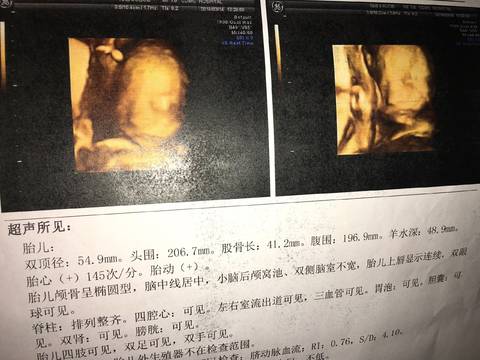

关于23周四维结果,S/D值偏高,说我的差不多是24周的临界点,是不是跟我以前做b超偏大10天左右有关系!怀孕后做了三次b超,都比正常孕周大10天左右。日期没有记错的相关问题在宝宝树孕育APP已经有26位专家做了权威的回答。